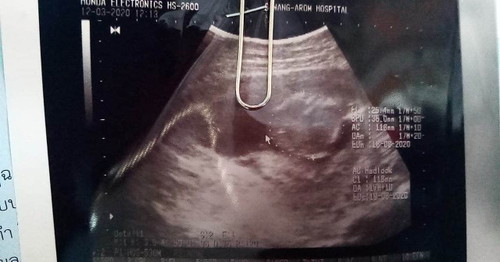

ในใบซาวมีวันกำหนดคลอดที่ตรงมั้ยค้ะ ตอนนี้น้อง8เดือนแล้วกลัวจะคลอดก่อนกำหนดเพราะเเม่จำวันที่ประจำเดือนหมดล่าสุดไม่ได้เลยได้บอกหมอวันที่ตรวจเจอไปค้ะ

หมอจะนับกำหนดคลอดจากการซาวครั้งแรกค่ะแม่ ตรงนะคะ